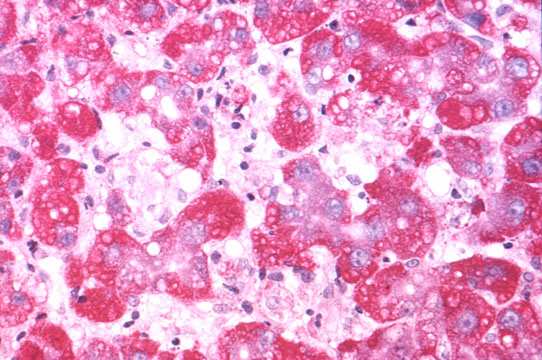

Kupffer cell hyperplasia

Fig 54 - KUPFFER CELL HYPERPLASIA: With cells full of lipofuscin an bile, result of phagocytosis of disrupted hepatocytes. Nodules of these cells may persist after healing (late nodules of Spatknoetchen).